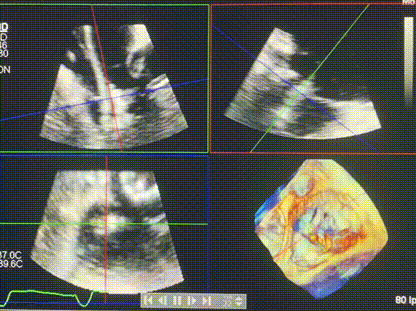

術(shù)中輸送器在超聲引導(dǎo)下調(diào)整位置

手術(shù)在全麻狀態(tài)下進(jìn)行。術(shù)者采用經(jīng)右側(cè)頸靜脈入路的方式將輸送器送入患者心臟內(nèi),在TEE及DSA引導(dǎo)下調(diào)整輸送器頭端角度,使得輸送器與三尖瓣瓣環(huán)平面垂直。在輸送器進(jìn)入右心室后釋放室間隔錨定裝置,而后釋放瓣葉夾持件(2個(gè)耳片結(jié)構(gòu))成垂直狀態(tài)。在TEE及DSA確定夾持件固定至三尖瓣葉根部且位于右室側(cè)后釋放人工瓣心房側(cè)盤片。隨后調(diào)整瓣膜同軸性以及室間隔錨定件位置(貼合室間隔),前推藏針管并固定,進(jìn)而釋放室間隔錨定裝置,并再次確認(rèn)瓣膜位置、穩(wěn)定性及同軸性,合攏輸送鞘后撤出輸送器,完成LuX-Valve Plus人工三尖瓣瓣膜的植入,僅殘余微量瓣周漏。且經(jīng)手術(shù)中心電生理團(tuán)隊(duì)評(píng)估,病人的起搏器和ICD功能沒有受到影響。

術(shù)后超聲顯示僅殘余微量瓣周漏